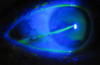

management? (2)

eye shield

+

[hospital admit (strict bed rest + 30° bed + serial intraocular pressures+ [prevent rebleeding and intraocular HTN → vision loss])]

HYPHEMA